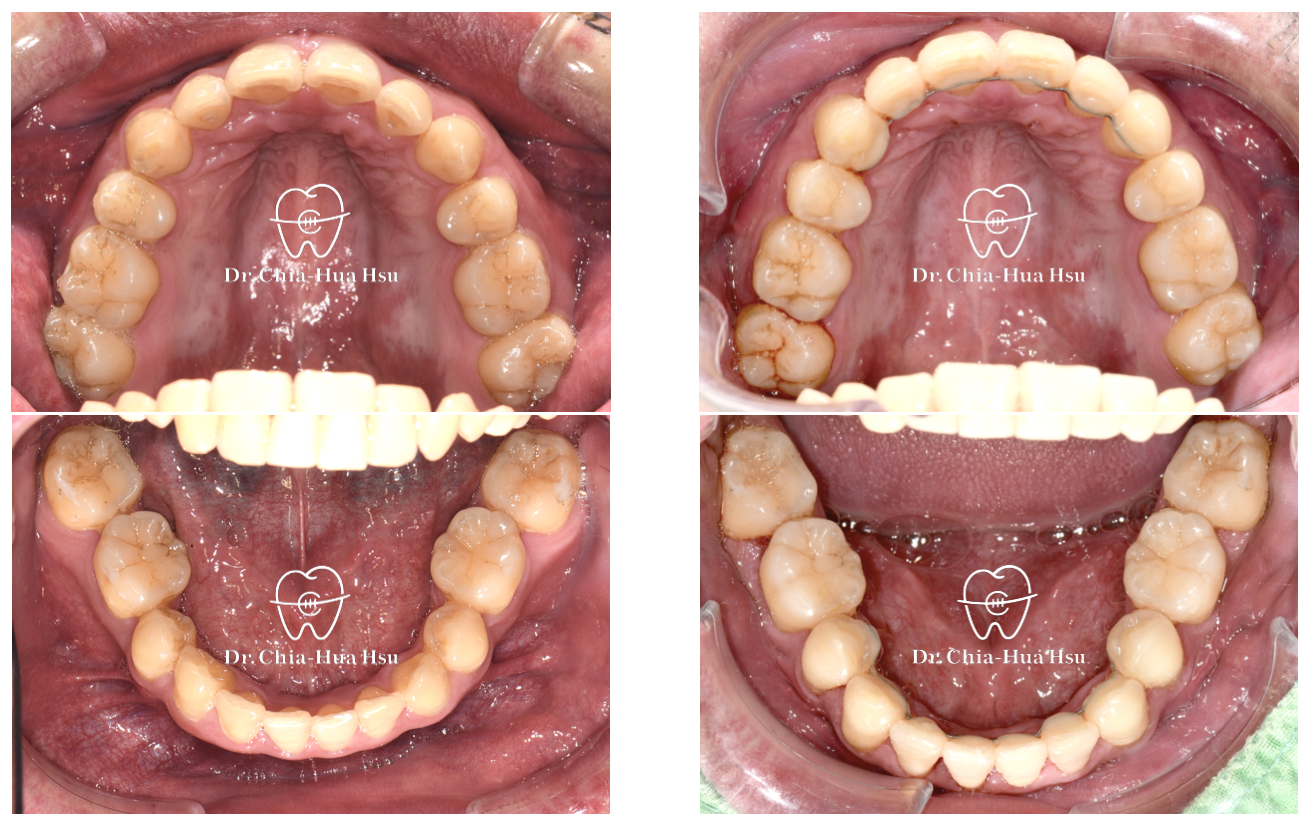

治療前

治療後